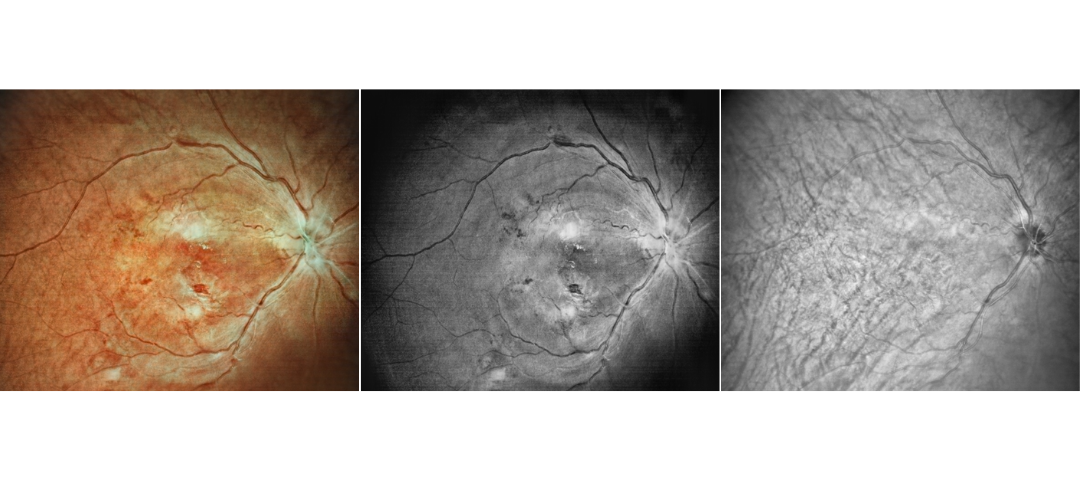

Scanning Laser Ophthalmoscope Obtain Retinal Layer and Choroidal Layer

Our scanning laser ophthalmoscope uses multi-wavelength laser scanning to penetrate the fundus, capture details of the retinal and choroidal layers, and obtain high-definition fundus images.

Retina Examination Under Cataracts

Examining fundus diseases through cataracts is a crucial topic in ophthalmology. Traditional fundus cameras cannot see through cataracts to capture fundus conditions. However, our DF600 scanning laser ophthalmoscope can penetrate moderate cataracts, providing a glimpse into the fundus and offering greater convenience for fundus examinations in patients with cataracts.

Fundus Cases Display

Our SLO makes fundus examination easier for you, capturing ultra-clear and wide-angle images of the retina and choroid, and then synthesizing color fundus images to present a rich picture of the fundus status.

High blood pressure, venous obstruction, and bleeding